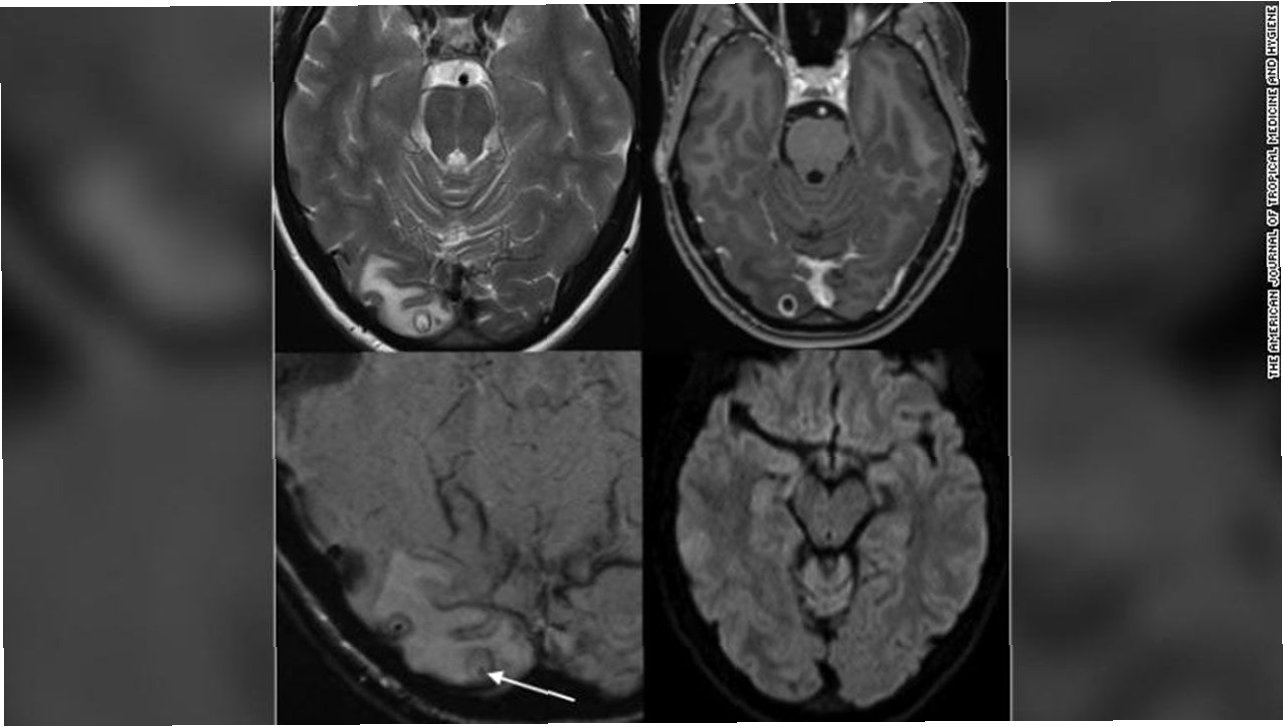

환자는 여러 검사에도 불구하고 기생충 감염의 명확한 흔적을 찾기 어려웠습니다. 세균, 곰팡이, 기생충 항체 검사 등에서 음성 반응이 나왔고, 구충제 처방에도 호흡기 증상이 쉽게 가라앉지 않았습니다. 수개월간 증상이 지속되면서 환자는 우울감과 기억상실까지 겪게 되었습니다. 결국 뇌 MRI 검사를 통해 우측 전두엽에서 병변이 발견되었고, 뇌 조직 검사 결과 살아있는 기생충이 확인되었습니다. 의료진은 뇌 조직에서 약 80mm 길이의 기생충을 제거하는 수술을 시행했습니다.